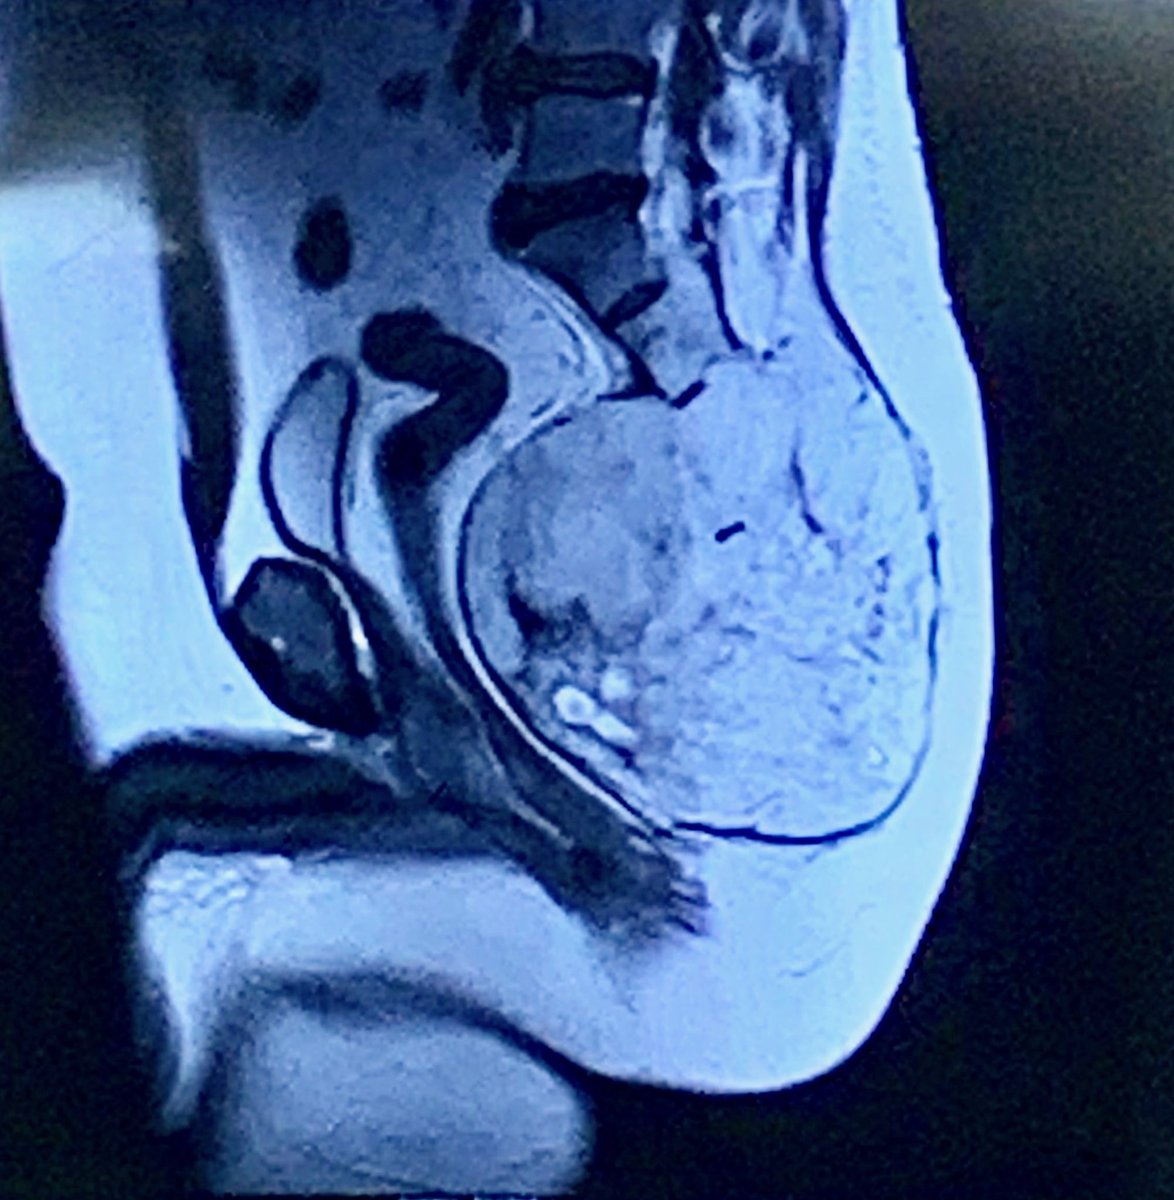

#Sarcoma Tumor Board:#Chordoma with physaliphorous cells. MRI shows large sacral location with extension into L4 and L5. Will require 3 surgical and 2 radonc specialties @SylvesterCancer .@jayloum1 @TSubhawong @raphaelyechieli @GinaDAmatoMD1pic.twitter.com/yYZV6ra7kY